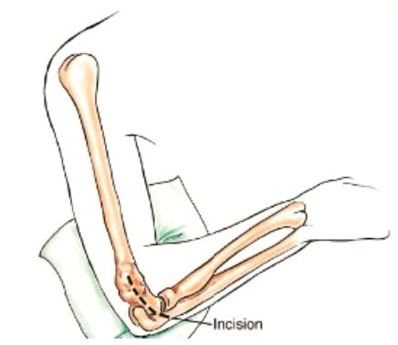

Incision

A long incision is made along the biceps muscle and the elbow joint is exposed using an s shaped incision from the long incision.